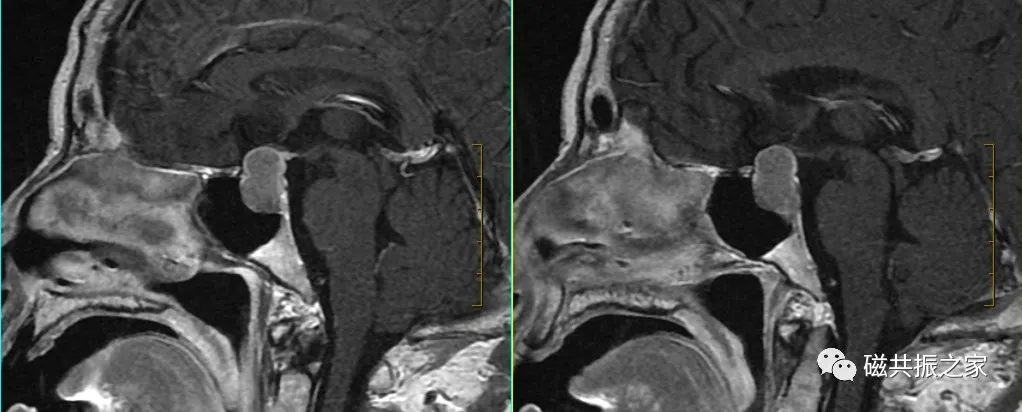

矢状位:SAGT1FSE矢状位T1加权序列

以冠状位和横断位作为参考定位。在横轴位上与大脑矢状裂平行;在冠状位上定位线与垂体柄平行,双侧对称扫描。FOV中心置于垂体位置,扫描范围包括整个垂体,根据病变大小调整范围,需包括整个病变范围。

矢状位是显示垂体前后叶最理想的方位。

在不同的年龄阶段,垂体的MRI信号有所不同,新生儿整个垂体在T1WI上表现为高信号,约6周以后,垂体前叶的信号强度逐渐减弱并最终与脑皮质相似,而垂体后叶组织内具有较多的神经分泌囊泡则表现为高信号,若高信号缺失则可能与中枢性尿崩症或垂体腺瘤受压有关。

腺垂体可以分泌多种激素,其在T1WI上呈相对低信号,与脑皮质信号相仿;神经垂体虽然不分泌激素,但其可储存下丘脑分泌的激素,在T1WI上常表现为高信号。